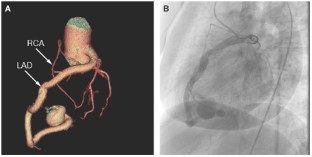

Investigations Physical examination, chest radiography, electrocardiography, transthoracic echocardiography, 64-slice multidetector CT and coronary angiography.

Diagnosis Fistula originating from the left anterior coronary artery and draining into the right ventricle, in conjunction with an aneurysm of the left anterior descending artery.

Versaci, F., Del Giudice, C., Sperandio, M. et al. A case of coronary artery fistula visualized by 64-slice multidetector CT. Nat Rev Cardiol 6, 57–60 (2009). https://doi.org/10.1038/ncpcardio1413